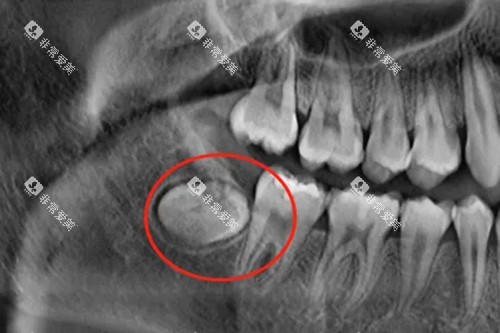

埋伏智齿:完全隐藏在颌骨内,需借助X光片定位,手术复杂度高,价格可能飙升至1500-4000元/颗。

“同样是拔智齿,为啥价格差这么多?”泉州海丝口腔的陈医生解释:“阻生智齿就像‘钉子户’,得用涡轮机、超声骨刀等工具‘拆墙’,而埋伏智齿甚至需要全麻手术,成本自然高。”